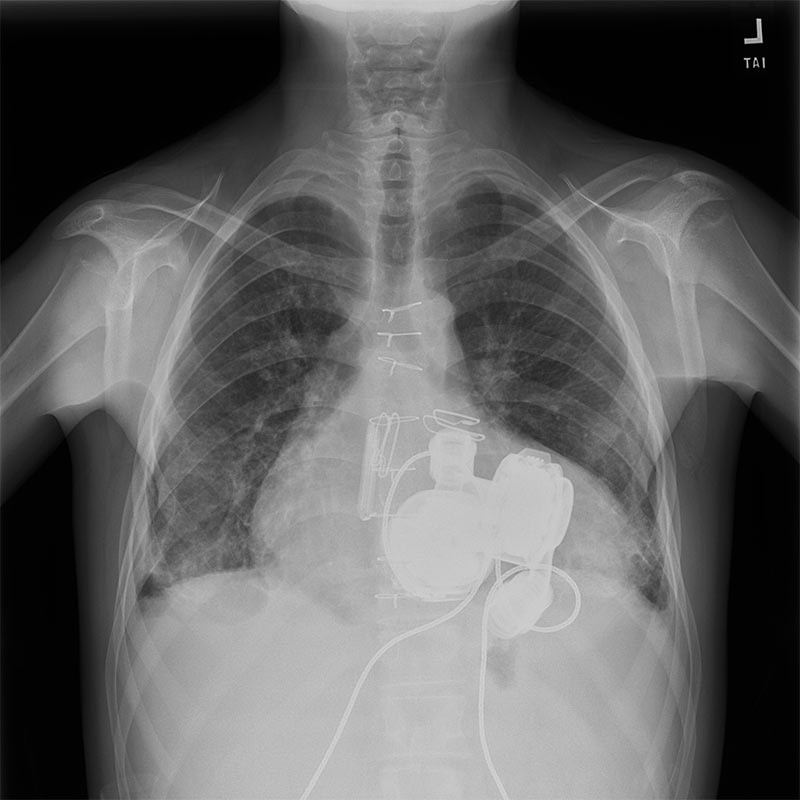

The HeartMate 6 (HM6) involves surgically implanting two commercially available HeartMate 3 (HM3) pumps — one configured as an LVAD and one as an RVAD — to function as a total artificial heart.

A robust, double-layered Dacron graft was sewn to the inflow points: the mitral annulus, for blood from the lungs to the LVAD and the tricuspid annulus for blood from the body to the RVAD. To prevent future bleeding, all remaining heart muscle and tissue were carefully oversewn in two protective layers.

The two HM3 pumps were then implanted. Their inflow cannulas were secured to the Dacron grafts, while the outflow grafts were connected to the major arteries: the left-sided pump to the aorta (end-to-end), and the right-sided pump to the pulmonary artery.

The final step involved placing a tissue expander preventing the chest cavity from collapsing. Since the two VAD pumps are significantly smaller than the native heart, the mediastinum would shrink, compromising a potential future transplant. A tissue expander was placed to keep the space open before the chest was closed.